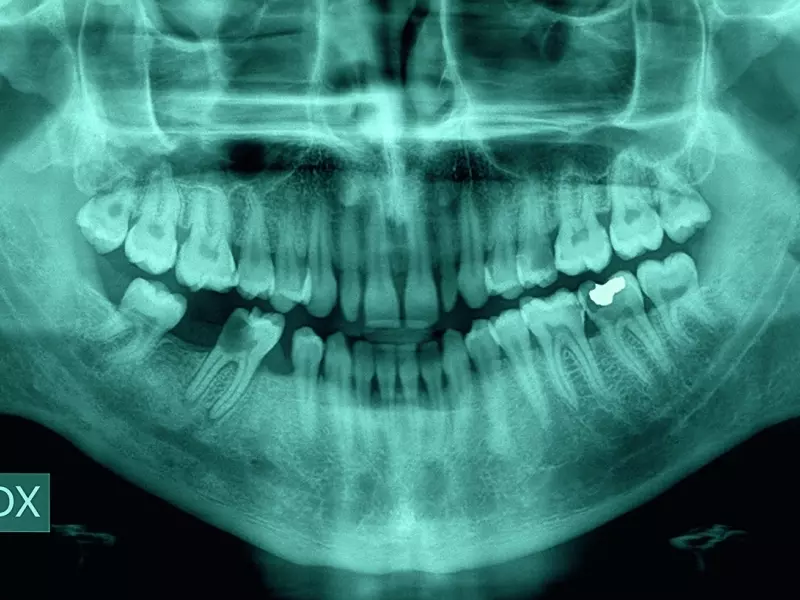

Kluczowym zagadnieniem związanym ze skutecznym leczeniem endodontycznym i długotrwałym przetrwaniem zębów leczonych endodontycznie jest eradykacja zakażenia bakteryjnego z całego systemu kanałów korzeniowych w zębie. Jednym ze sposobów na zwiększenie skuteczności eliminacji bakterii z kanałów korzeniowych jest zastosowanie laserów stomatologicznych.

Warunki chemofizyczne w kanale korzeniowym przyczyniają się do selekcji gatunków bakterii w trakcie rozwijającej się infekcji systemu korzeniowego, która jest związana głównie z bakteriami: Enterococcus faecalis, Streptococcus anginosus i Fusobacterium nucleatum.

Najwięcej problemów z eliminacją bakterii stwierdzono w przypadku jednej trzeciej dowierzchołkowej części korzenia zęba, gdzie mamy do czynienia z najmniejszym stopniem poszerzenia ścian kanału, a ponadto często występują dodatkowe rozgałęzienia i boczne kanały delty korzeniowej. Każdy sposób wspomagający dezynfekcję w tej okolicy w trakcie leczenia endodontycznego stanowi cenne uzupełnienie tradycyjnego sposobu postępowania.